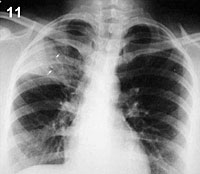

Comentario placa 11: Se observa una condensación no homogénea que compromete el lóbulo superior derecho, limitando parcialmente por abajo con la cisura horizontal (H). Dentro de la condensación es posible observar algunas sombras lineales ramificadas (B), más oscuras en la placa, que corresponden a un broncograma aéreo.